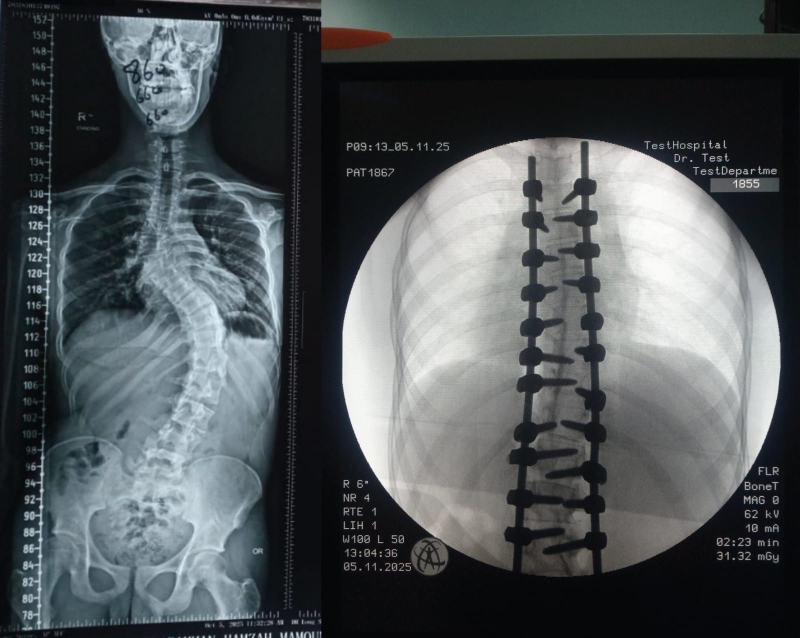

خبرني - شهد قسم جراحة العمود الفقري في مستشفى الأمير حمزة إنجازًا طبيًا مميزًا تمثّل في إجراء تدخّل جراحي معقّد لتصحيح جنف العمود الفقري لدى أحد المرضى الذين يعانون من تشوّه حاد في الفقرات.

وقد أُجريت العملية باستخدام جهاز الملاحة الجراحية المتقدّم، الذي أتاح دقةً عالية في التعامل مع التشوّهات البنيوية الشديدة، وسهّل توجيه الأدوات الجراحية ضمن المسار الآمن والمثالي.

كما اشتملت العملية على إزالة أجزاء محددة من الأطراف الخلفية للفقرات لتحقيق التصحيح المطلوب واستعادة التوازن والمحاذاة الطبيعية للعمود الفقري.

وتم تنفيذ هذا الإجراء الدقيق تحت نظام مراقبة الأعصاب المتواصل (Intraoperative Neuromonitoring) لضمان سلامة الوظائف العصبية طوال مراحل العملية.

وقد نُفّذ هذا التدخل الجراحي بقيادة الدكتور إبراهيم القاسم، أخصائي جراحة العمود الفقري والتشوّهات الخَلقية، والدكتور محمد الطراونة، رئيس قسم جراحة الأعصاب، وبمشاركة كلٍّ من المقيمين: د. محمد محمود نعمان (مقيم جراحة الدماغ والأعصاب)، ود. أحمد الرواشدة (مقيم جراحة العظام)، إضافةً إلى فريق التخدير برئاسة الدكتور راسم عبدالرزاق